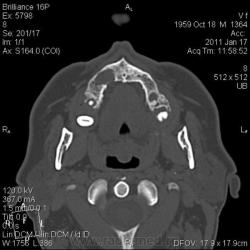

КТ головного мозга. Случайная находка. Жалоб "на челюсти" нет.

Мужчине 51 год. Периферический рак легкого. Очаговых изменений головного мозга не нашла. Пациент не критичен к своему состоянию (никуда не поеду, пусть как есть остается), поэтому отсутствие жалоб еще ничего не значит.

Контуры внутренние деструктивной полости изъеденные, кость вздута, но внешне не видно. В центре уровень?  с плотностью 30 ед.Н. Адамантинома? С зубными делами практически не сталкиваюсь. Нужна Ваша помощь. Какие будут идеи, уважаемые коллеги?

Конечно, одно другому не мешает... Написала адамантиному под вопросом, рекомендовала консультацию стоматолога. На мтс вроде не очень похоже, на остеомиелит - тоже.  Мягкотканного компонента - нуль. Как найду что-нибудь... и с большими глазами сюда)).

На мой взгляд процесс был, да прошел. Состояние после апикальной кисты удаленного зуба

Я думаю, это радикулярная киста с вторичным гиперостозом стенок воспалительного характера. Не уверен, что это состояние можно назвать остеомиелитом.

На метастаз и адамантиному непохоже.

До кабинета стоматолога дело не дошло. Просто триллер получился... пациент отказался от осмотра, мол, выписывают, как заболит - пойду в поликлинику. А когда пришел за диском с DICOM, у меня в ординаторской была стоматолог. Ей-богу случайно!)) Осмотрели ротовую полость. Хоромlaugh. Слизистая совершенно нормальная. Потом мы тем же хором его анамнестически "пытали" - каждое слово вытягивая словно клещами. Затащить в стомат.кресло не удалось, но вывод стоматолога после просмотра КТ таков - вероятнее всего, киста с периодическим нагноением.

Случай в свое время прошел мимо. Интересный случай. Да, и в нижней челюсти, по всей видимости, имеет место патология.